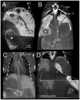

Intrasplenic hematoma